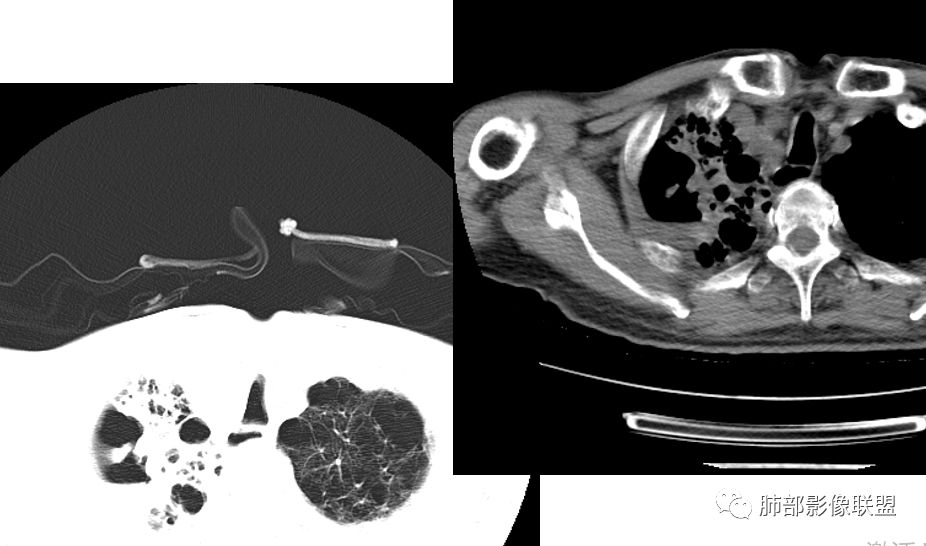

病例分析:双肺肺气肿,肺大泡,右肺上叶大片实变及空洞影,空洞壁光滑,部分有液平,病变自胸膜下向内,胸膜增厚,右肺下叶实变伴有空洞,右侧胸水,右肺门淋巴结肿大 ,抗炎治疗后变化不大,临床起病一周,有发热,血沉及降钙素高,肿瘤标志物稍高,结核干扰素阳性,首先考虑结核,鉴别细菌(空洞有液平)。

如果没有结果,分析是这样:这个人肺气肿基础,出现大片实变,那符合气肿性肺炎,头两次影像上还看不出结核来,但是白细胞不高,中性粒仅仅高一点的,然后血沉高,R干扰素高,抗感染不好。然后这个人有老年痴呆,初期可能会考虑这个人会不会只是一个细菌性肺炎呢,进展快。入院常规给与抗细菌没有问题。但是到11.08号影像出现一些端倪。一般气肿性肺炎虽然说可能好的不那么快,但是给与了亚胺培南这么高级的药反而进展,再加上血常规和一些实验室检查,好像普通细菌感染就有一点说不过去了。到第三次,出现空洞了,和肺气肿肺炎的气肿已经不一样了,气肿随着实变增加,里面应该会填实才对,但是出现空洞,这个说明不再是气肿里面的,而是真的空洞,而且还是那种肺尖的、光滑、有壁结节的空洞。

增强后里面密度整体低,比较支持坏死,一般炎症强化比较高,会有毛细血管新生,这个强化太低,提示坏死性炎症。这个还蛮符合干酪样坏死,实验室也支持。结核我感觉肯定有。